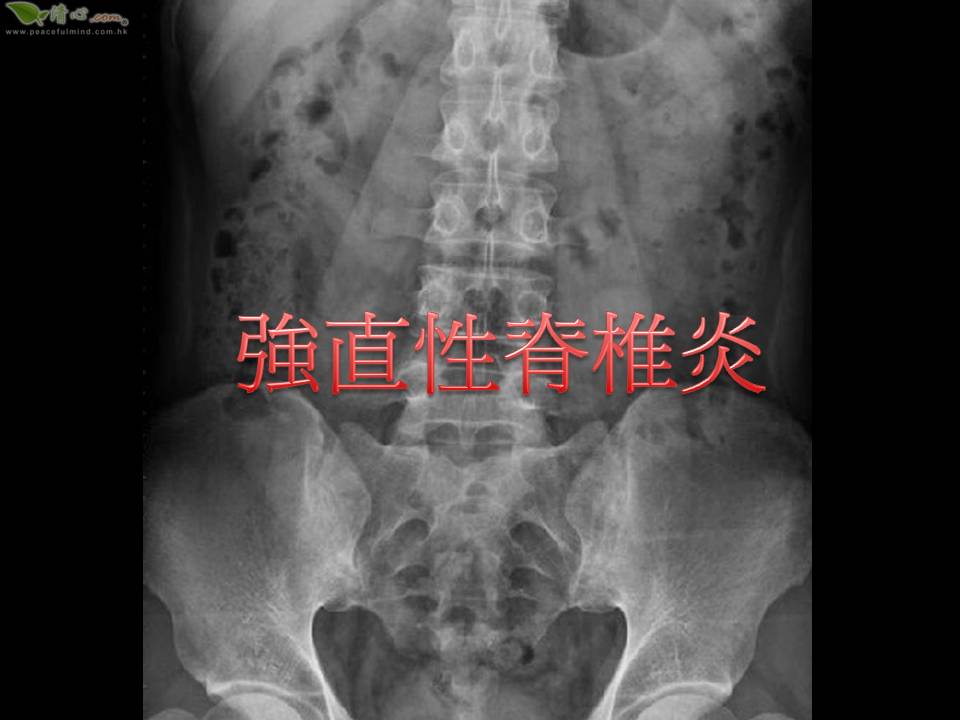

强直性脊椎炎

健康知识

健康知識